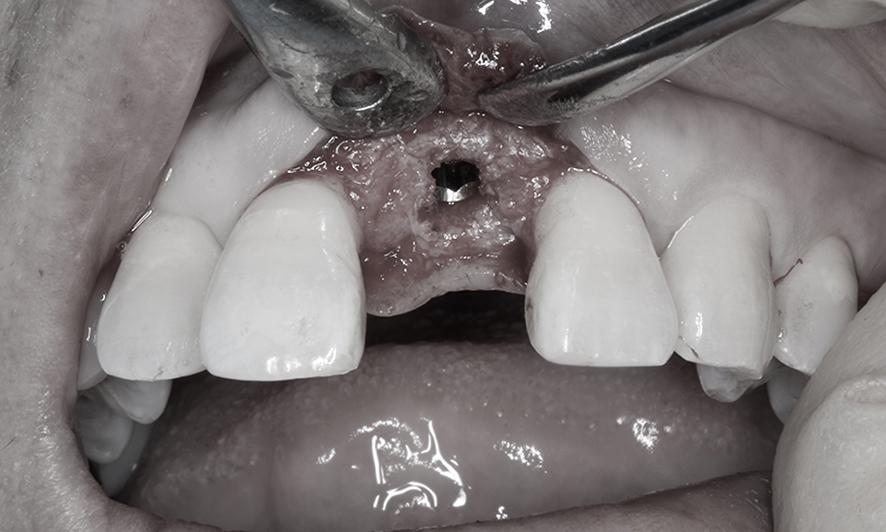

CTスキャンを用いて骨と歯肉の状態を精査したところ、骨の厚さはインプラントに適しているものの、歯ぐきの高さが不足していることが判明しました。そこで、インプラント手術と同時に「結合組織移植術(CTG)」を行い、歯ぐきの高さと厚みを補う計画をご提案しました。

手術では、事前シミュレーションで決定した理想的な位置にインプラントを埋入するため、「埋入ガイド(ステント)」を用いて精密に処置を行いました。さらに、歯ぐきを慎重に剥離し、必要な厚さを盛り足して縫合しました。

インプラント埋入と同時に結合組織移植術のために、部分層弁という手法で一部の歯茎を慎重に剥がします。